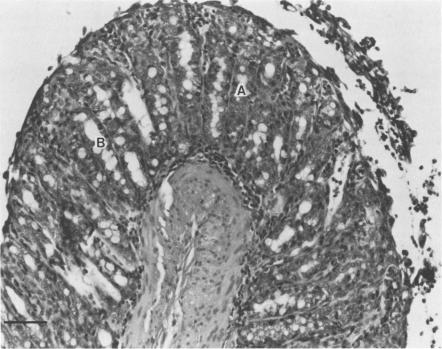

We tested the usefulness of the Removable Intestinal Tie Adult Rabbit Diarrhea model to establish Campylobacter jejuni infection in rabbits. The procedure involved ligation of the cecum, placement of a slip knot at the terminal ileum, and injection of the test inoculum into the mid-small bowel. The ends of the slip knot were externalized, and the tie was released 4 h later. Fifty-five rabbits received C. jejuni, and 16 received uninoculated medium as controls. Daily rectal swabs were positive for 2 weeks in infected rabbits. The diarrheal attack rate was 64% in infected rabbits and 0% in controls. Diarrhea was characterized by loose, mucus-containing stools after an incubation period ranging from 24 h to 6 days. When blood was obtained daily for culture from 30 rabbits for 4 days post-challenge, bacteremia was present in 96.3% 24 h after challenge but diminished to 5 of 19 (26.3%) at 96 h. Death occurred in 53% of rabbits and was always preceded by diarrhea. No control animal died. Only 5 of 35 animals experiencing diarrhea recovered. An indirect whole-cell enzyme-linked immunosorbent assay was used to determine serum immunoglobulin G responses. Mean titers rose from 1:198 preoperatively to 1:9,087 on day 28. Necropsy on eight infected and two control animals showed inflammatory lesions with ulceration in 62.5% and goblet cell hyperplasia in 75% of infected rabbits. We conclude that the Removable Intestinal Tie Adult Rabbit Diarrhea procedure is a simple, effective method to establish C. jejuni infection which mimics human disease.

我们测试了可移除肠道结扎成年兔腹泻模型在兔中建立空肠弯曲菌感染的实用性。该操作包括结扎盲肠、在回肠末端放置一个活结,并将测试接种物注入小肠中部。将活结的两端引出体外,4小时后松开结扎。55只兔接种空肠弯曲菌,16只接种未接种的培养基作为对照。感染兔的每日直肠拭子在2周内呈阳性。感染兔的腹泻发作率为64%,对照组为0%。腹泻的特征是在24小时至6天的潜伏期后出现稀便、含黏液的粪便。在攻毒后4天,每天从30只兔采集血液进行培养,攻毒后24小时菌血症发生率为96.3%,但在96小时时降至19只中的5只(26.3%)。53%的兔死亡,且死亡前均有腹泻。无对照动物死亡。35只出现腹泻的动物中只有5只恢复。使用间接全细胞酶联免疫吸附试验来测定血清免疫球蛋白G反应。平均滴度从术前的1:198升至第28天的1:9087。对8只感染动物和2只对照动物进行尸检,发现62.5%的感染兔有炎症性病变伴溃疡,75%有杯状细胞增生。我们得出结论,可移除肠道结扎成年兔腹泻操作是一种简单、有效的建立空肠弯曲菌感染的方法,该方法可模拟人类疾病。